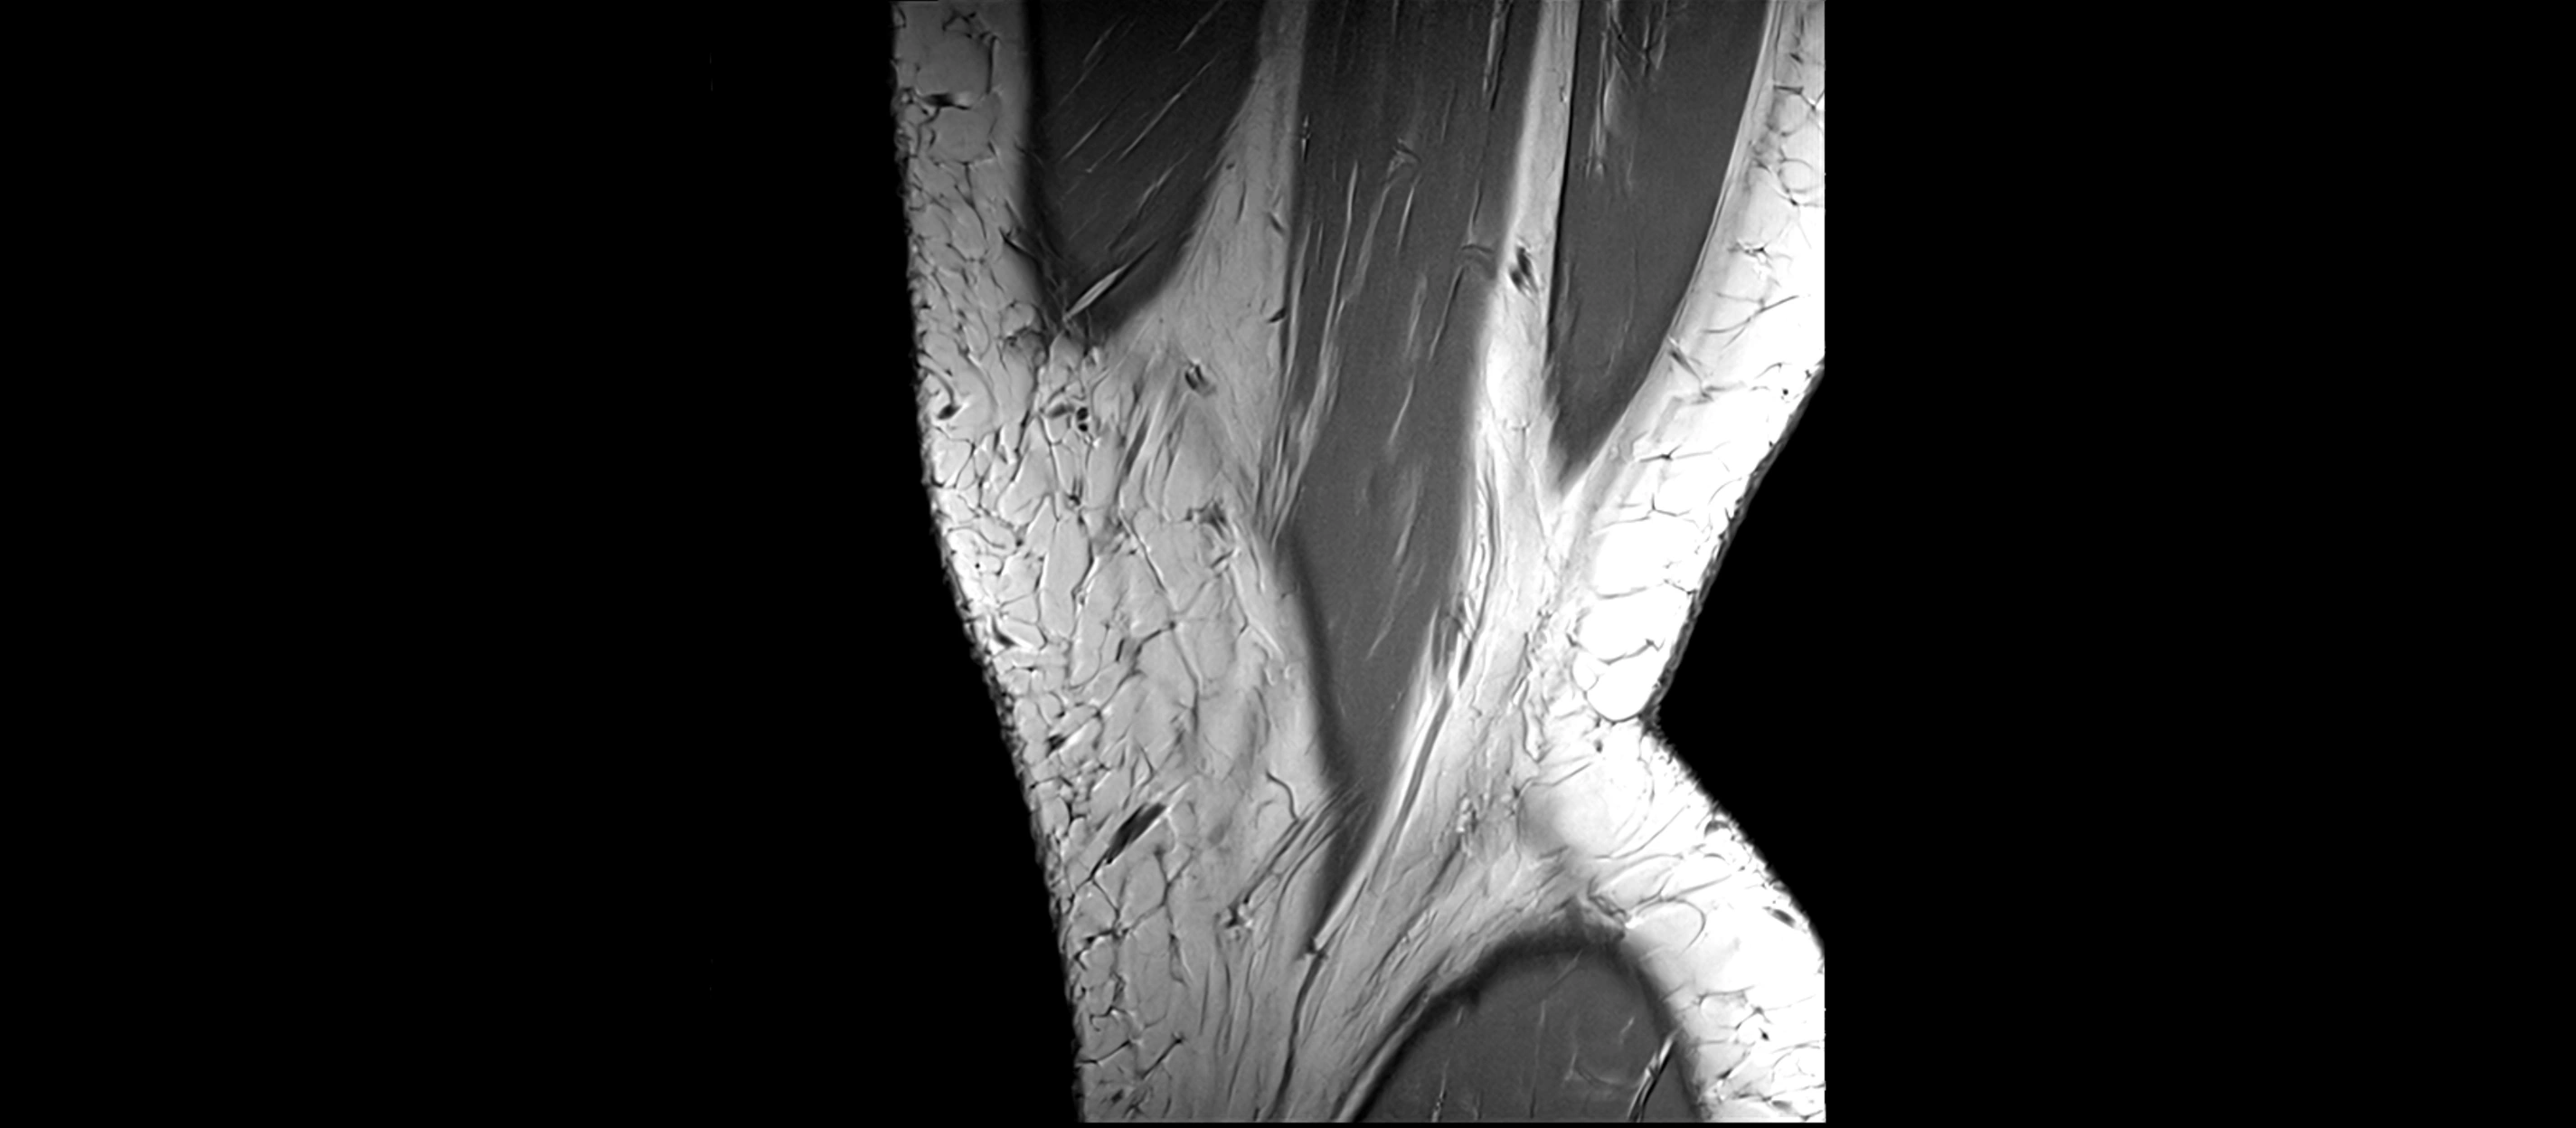

MRI images

image